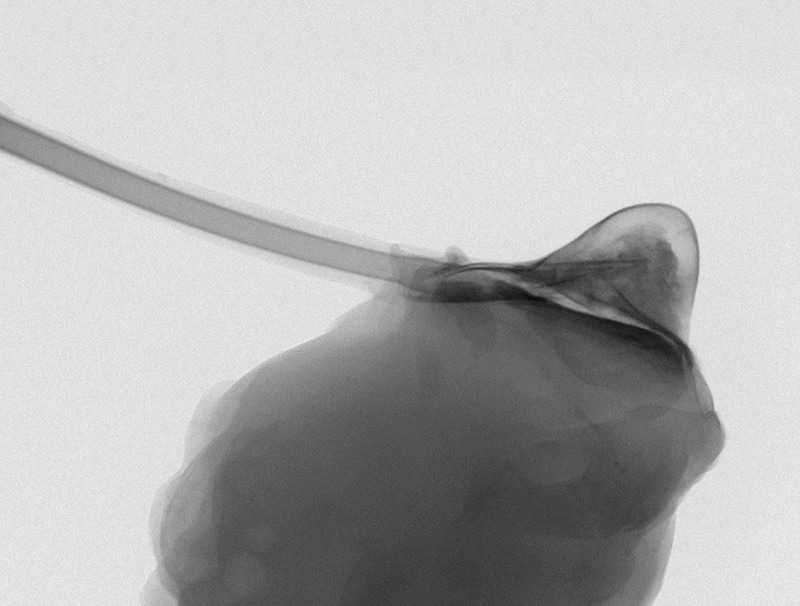

Arriva “Therepi”, un microscopico serbatoio di farmaci che si attacca direttamente al cuore e che può essere riempito dall'esterno in modo semplice grazie a un “tubicino” di collegamento che finisce sotto cute.

Therepi - fatto di un polimero gelatinoso a forma di semisfera con la parte schiacciata che si attacca al cuore - può anche rilasciare cellule per veicolare terapie cellulari che riparano il cuore nelle aree danneggiate da infarto. «Dopo un infarto potremmo usare questo apparecchio per rilasciare terapie preventive contro l'insorgere dell'insufficienza cardiaca», spiega Ellen Roche, coautore del lavoro del MIT, Institute for Medical Engineering & Science.